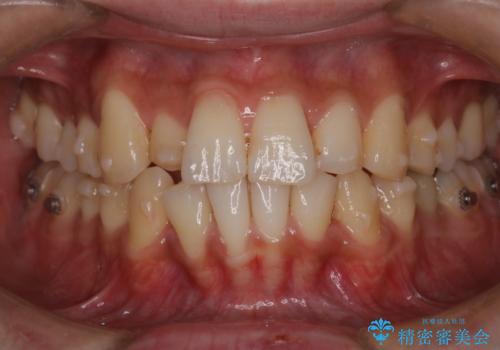

- 凸凹を治したいと来院された患者様です。

インビザラインにて、遠心移動を行いながら綺麗に配列することができました。

側切歯が低位の場合、反対咬合を改善した後に挺出させるのはワイヤーの方が適しています。